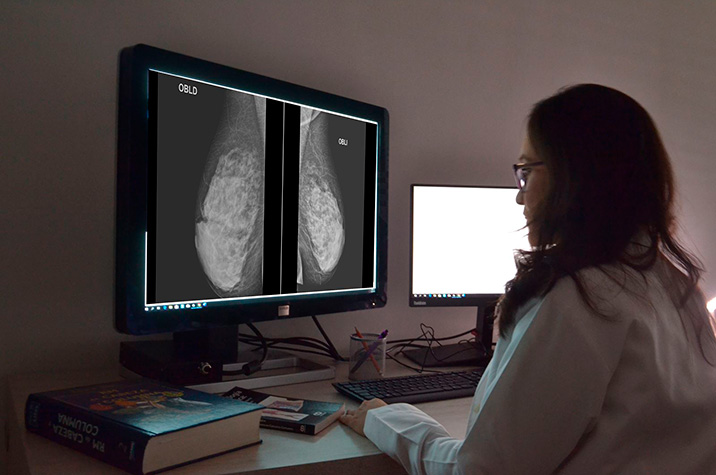

Eficacia comparativa de las ayudas para la toma de decisiones sobre los exámenes de detección del cáncer

Las ayudas para la toma de decisiones (AD) mejoran la toma de decisiones compartida sobre los exámenes de detección del cáncer al aumentar el conocimiento sobre los exámenes de detección del cáncer y la elección informada y reducir los conflictos en las decisiones, y pueden facilitar la participación individualizada y basada en las preferencias en los exámenes de detección. Los datos comparativos sobre los diferentes AD de los exámenes de detección del cáncer son limitados. J Gen Intern Med, 4 de septiembre de 2024.